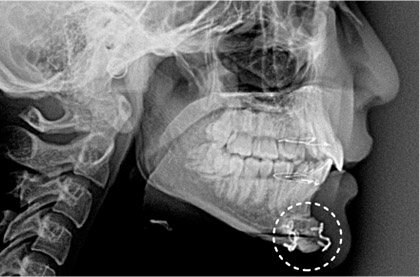

「笑うと頬が前方に盛り上がる」「正面から見た際に頬が横に出っ張っている」という際には、頬骨の骨切り・骨削り、さらに頬骨セットバックなどが適応となります。頬骨の突出は特にアジア人に多く見られ、顔が前面もしくは横に大きく見える他、頬骨が張り出していることでフェイスラインが凸凹になり、ゴツゴツした男性的な印象を与えてしまうこともあります。頬骨整形には骨切り術・骨削り術・頬骨セットバックがありますが、頬骨の張り出している方向や張り出しの強度、施術の範囲などによって実施する術式が異なります。